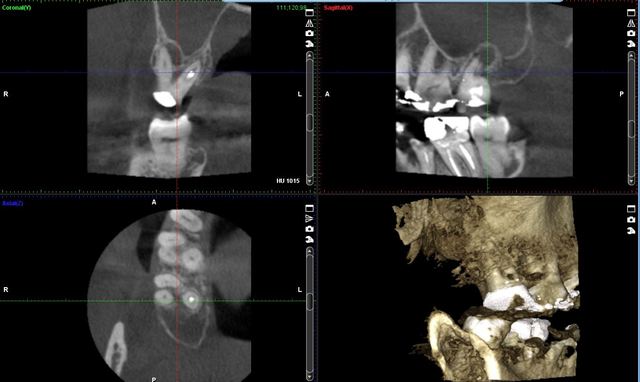

(TCHC –Tomógrafo Computerizado de Haz Cónico–, o CBCT –Cone Beam Computed Tomography, Europa (1997-1999)

Introducidas a raíz de los trabajos elaborados en el Proyecto Phidias